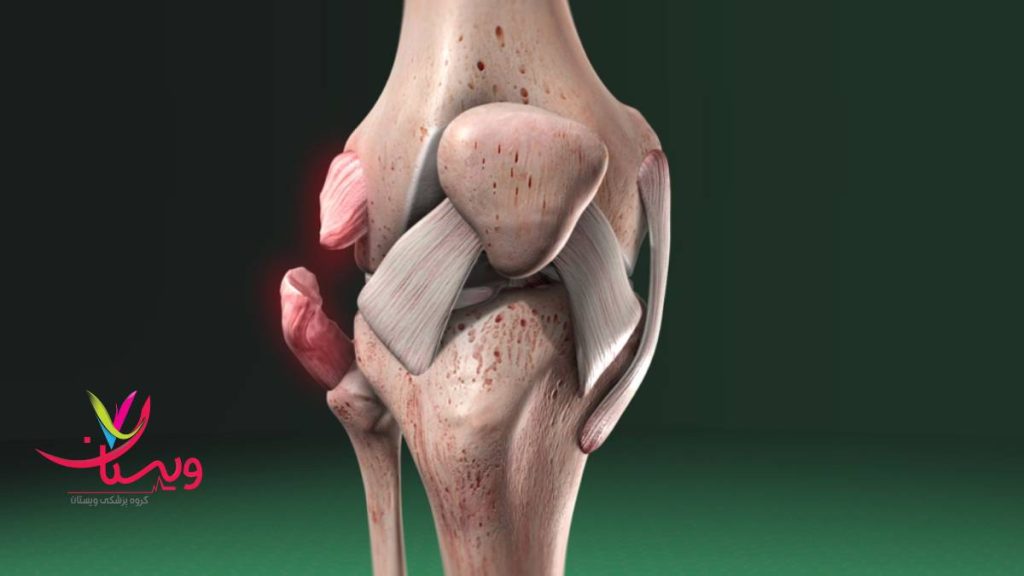

تست پارگی رباط جانبی زانو

تست پارگی رباط جانبی زانو یکی از مهمترین روشهای تشخیصی برای بررسی آسیبهای وارد شده به رباطهای داخلی (MCL) و خارجی (LCL) زانو است. این رباطها وظیفه پایداری جانبی زانو را بر عهده دارند و در اثر ضربه مستقیم، پیچش ناگهانی یا حرکات ورزشی سنگین دچار کشیدگی یا پارگی میشوند.

در هنگام آسیب، فرد معمولاً با درد موضعی در بخش داخلی یا خارجی زانو، تورم، کبودی و گاهی بیثباتی در حرکت مواجه میشود. پزشک با انجام تستهای بالینی میتواند میزان آسیب را ارزیابی کرده و در صورت نیاز از تصویربرداری مانند MRI برای تأیید نتیجه استفاده کند.

تشخیص سریع، بهویژه در ورزشکاران، اهمیت زیادی دارد زیرا درمان به موقع مانع از آسیبهای ثانویه به مفصل زانو میشود. درمان شامل استراحت، استفاده از بریس، فیزیوتراپی و در برخی موارد جراحی است.